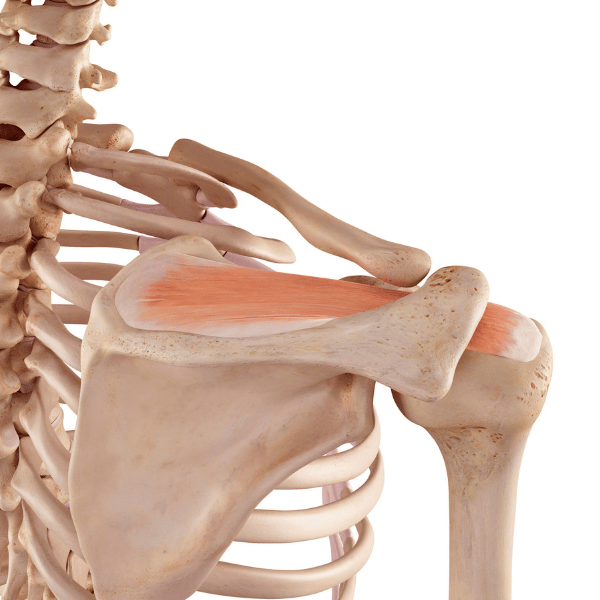

Gre za progresivno deformacijo, pri kateri je prizadet sklep palca na stopalu – metatarzo-falangealni (MTP) sklep, ki ga pogosto spremljajo funkcionalne okvare in bolečine v stopalih. Sklep se postopoma subluksira oz. premakne iz svojega prvotnega položaja, kar povzroči odmik prve metatarzalne kosti, medtem ko se členki palca in kazalca primaknejo skupaj.

Odmik palca posledično privede do nastanka mehkega tkiva in kostnega izrastka na medialni (notranji) strani palca. Te spremembe v pozni fazi vodijo do bolečin in omejitev gibanja. Težave se najpogosteje pokažejo že pri hoji, ki postane boleča, poslabša se ravnotežje, itd.

Nožni palec oz. hallux je sestavljen iz metatarzalne kosti ter iz proksimalne in distalne falange. Gibanje nožnega palca zajema upogib (krčenje palca), izteg (dvig palca) in odmik. Na palec se pripenja kar sedem mišic, ki omogočajo mobilnost in stabilnost palca.

Pri hoji je zelo pomembno, da lahko dosežemo normalen izteg palca, kar se zgodi v fazi odriva. Nepopoln izteg palca negativno vpliva na stabilnost stopalnega loka in plantarno fascijo. V primeru hallux valgusa je gibljivost palca zmanjšana in eden od pomembnejših gibov, ki ga moramo ponovno pridobiti, je ravno izteg.